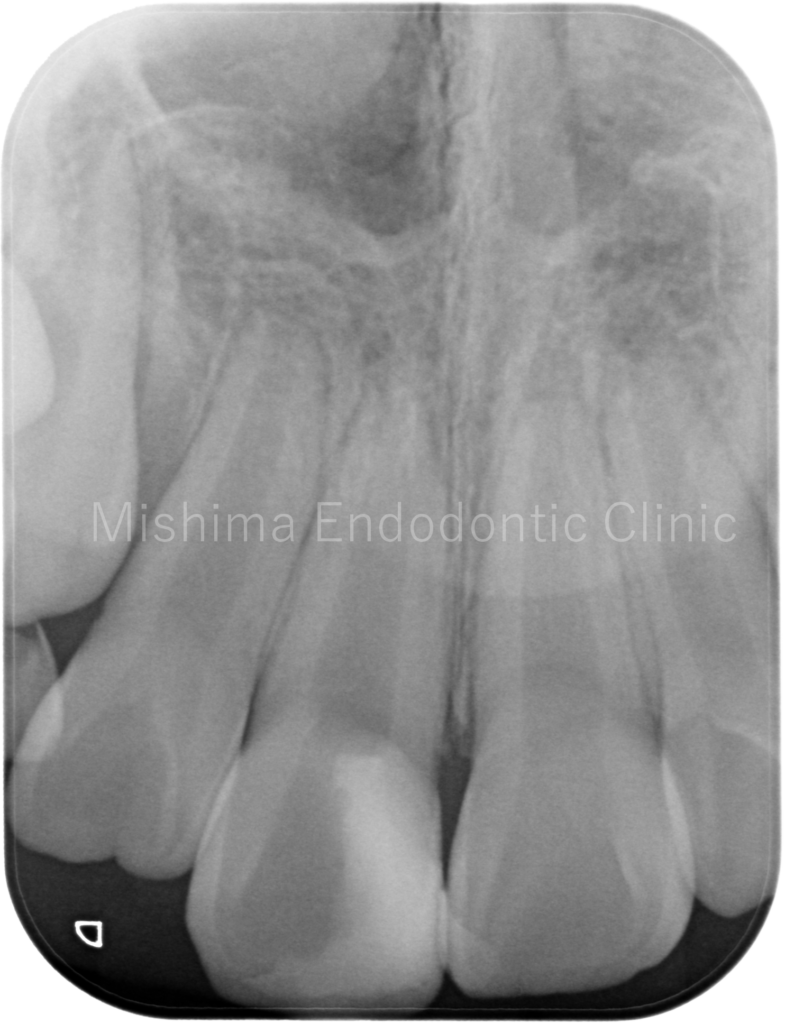

術後1年7カ月

| 治療内容 | 転倒により露髄を伴う歯冠ー歯根破折を認めた。部分断髄とダイレクトボンディングにて修復。審美的配慮から、バイオデンティンを選択。術後、経過は良好。 |

| リスク・副作用 | ・歯髄保存療法が奏功しなかった場合、根管治療へ移行します。 ・根管治療が必要となった場合、修復物を除去することがあります。 ・保険診療範囲外の自費診療になるため費用が高くなる場合があります。 ・術後に歯髄が壊死する可能性があります。 |